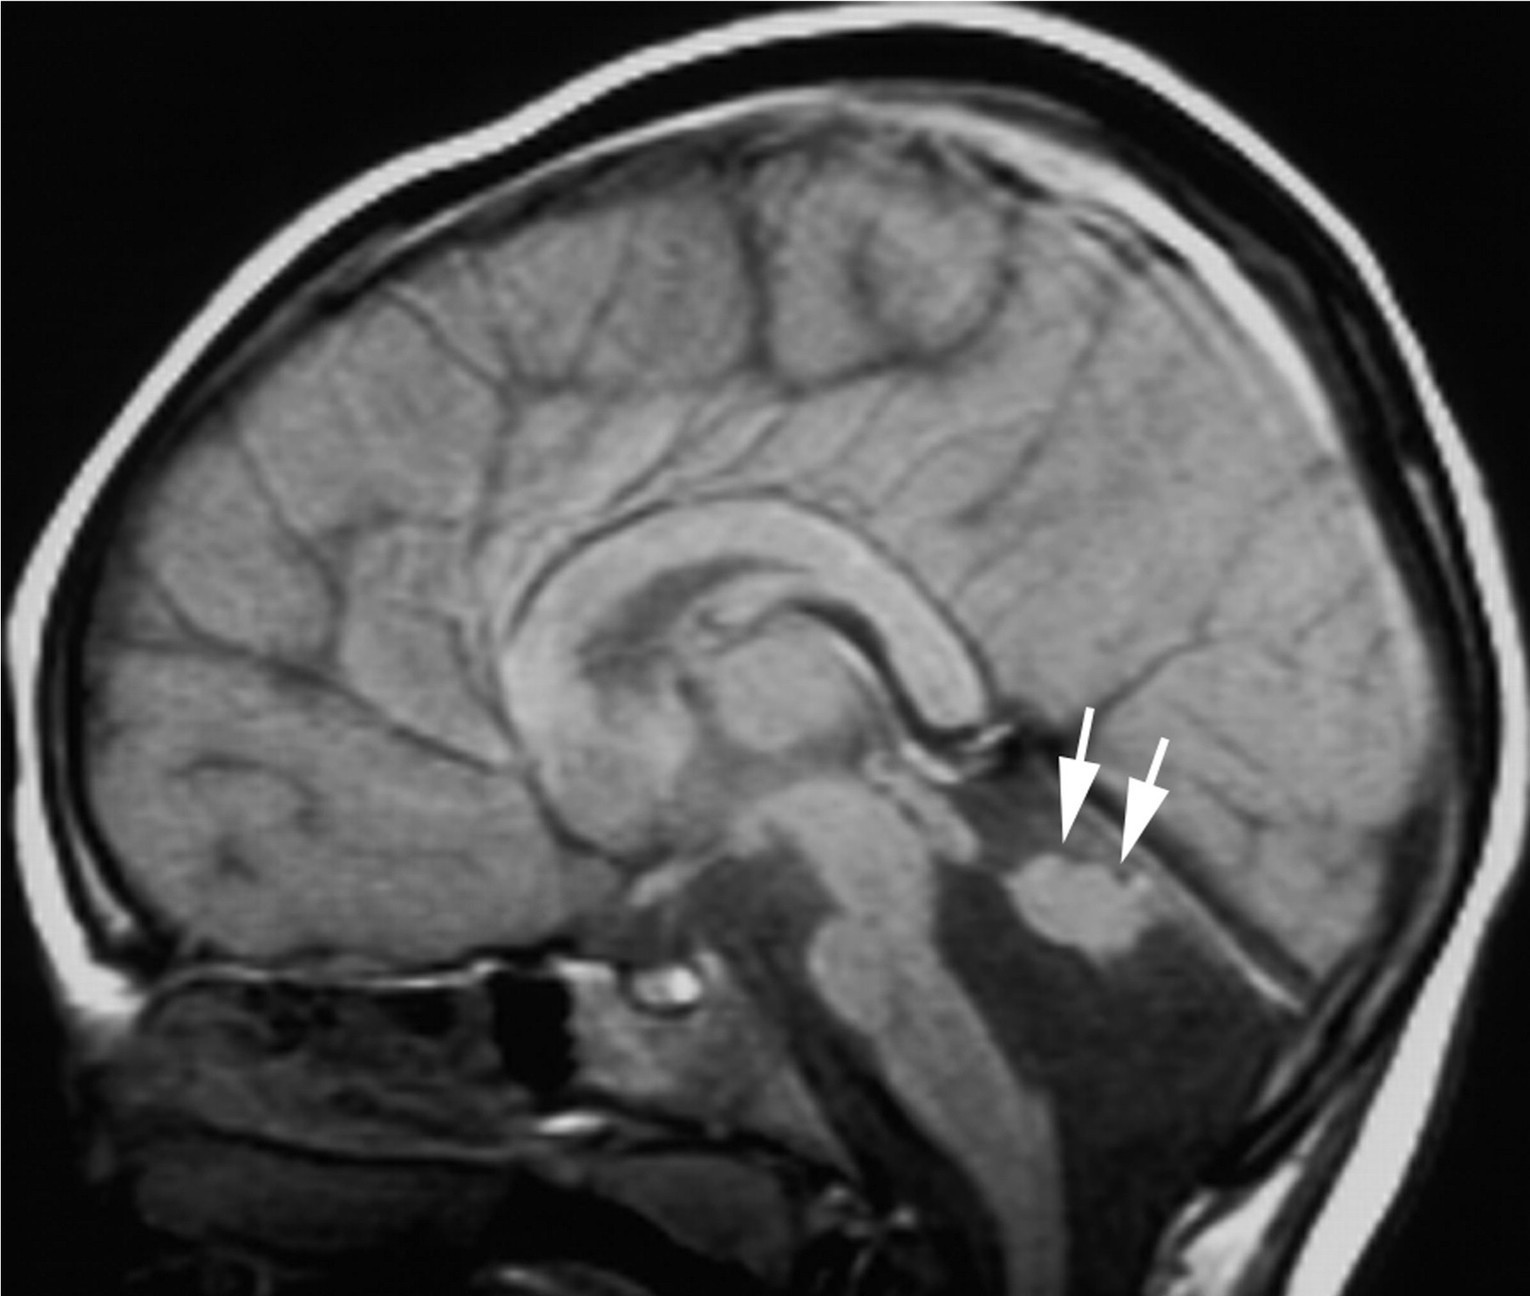

Beyin Emari Nasil Cekilir Oncesi Ve Sonrasi Hazirliklar Ve Asamalar